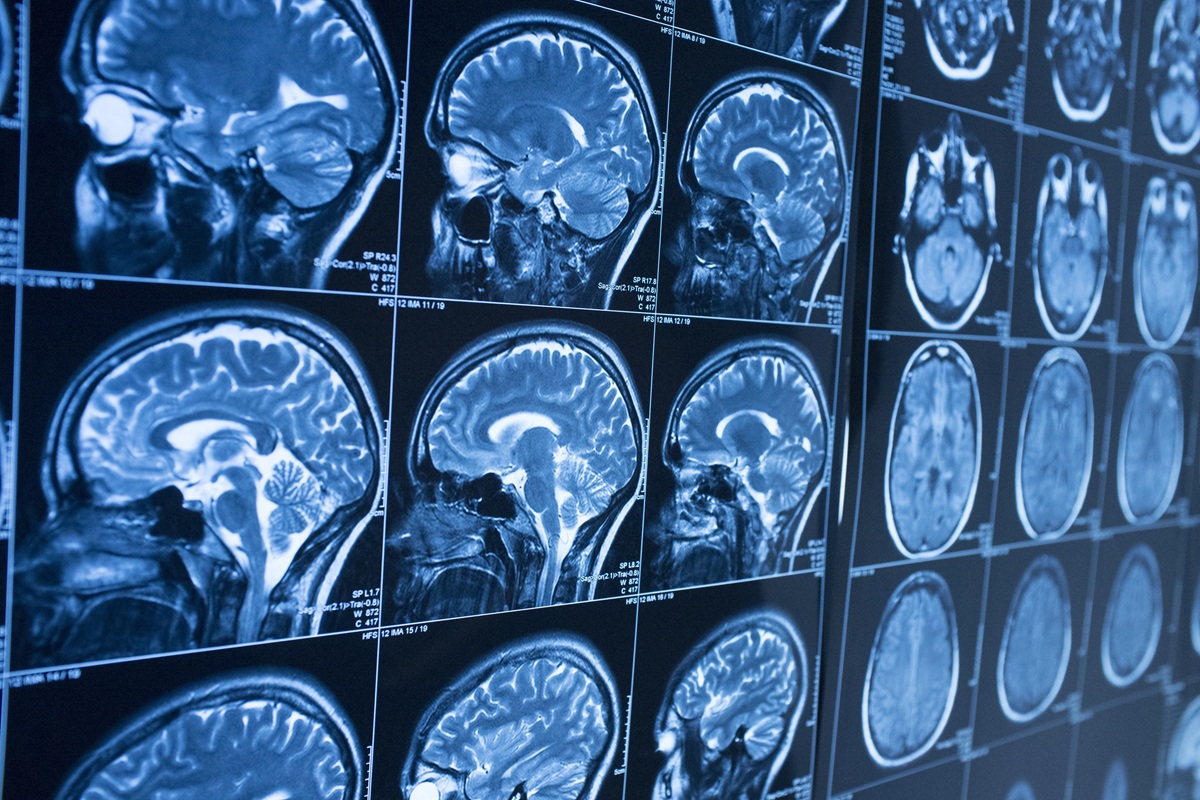

Munson detalhou que “o que observamos é uma contração dos vasos linfáticos e uma diminuição de suas alças ou ramificações. Esses são sinais de um crescimento reduzido que indicam que os vasos linfáticos estão mudando ou não se regenerando de forma benéfica. A saúde linfática deteriorou-se significativamente nos três modelos, medidos de diferentes maneiras”. Não existe uma cura definitiva para o quimio-cérebro, mas terapias e hábitos saudáveis podem aliviar os sintomas As imagens cerebrais em ratos tratados com o medicamento revelaram um drenagem linfática reduzida, e os testes cognitivos mostraram que estes animais apresentavam déficits de memória. Munson acrescentou que “isso poderia explicar potencialmente alguns desses déficits de memória, o que é semelhante ao que vimos na doença de Alzheimer”.